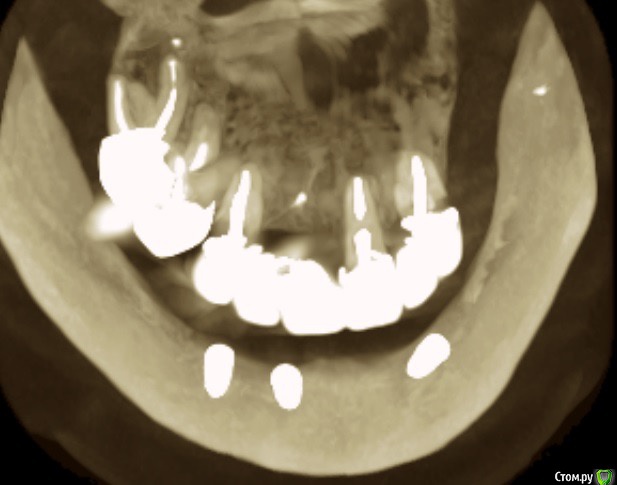

Andre_ Опубликовано 17 марта, 2016 Поделиться Опубликовано 17 марта, 2016 Из анамнеза : Ж, 25 лет, HCv, финансы на зубы лимитированы. Фото 1 до, фото 2 и 3 - около 5 мес. Ортопед хотел/хочет шаровидные абатменты и условно съёмный. Фото во рту утеряно, простит : Биотип тонкий, в позиции 3.3 вместе с шурупом НКР, успешно сьедено, вторичке. Сейчас шея и витки светятся через слизистую. Подвижная слизистая начинается по вершине гребня. Цель - изобразить пкд вокруг имплантов, что посоветуете? Есть смысл углублять преддверие, если да - как? Буду признателен совету, пока план дальнейших действий невразумительный. Ссылка на комментарий